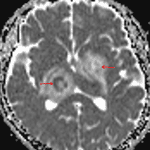

CT

- Ill-defined hypoattenuating areas involving the left basal ganglia, right thalamus, and bilateral internal capsule

- Internal foci of hyperattenuation

CNS toxoplasmosis